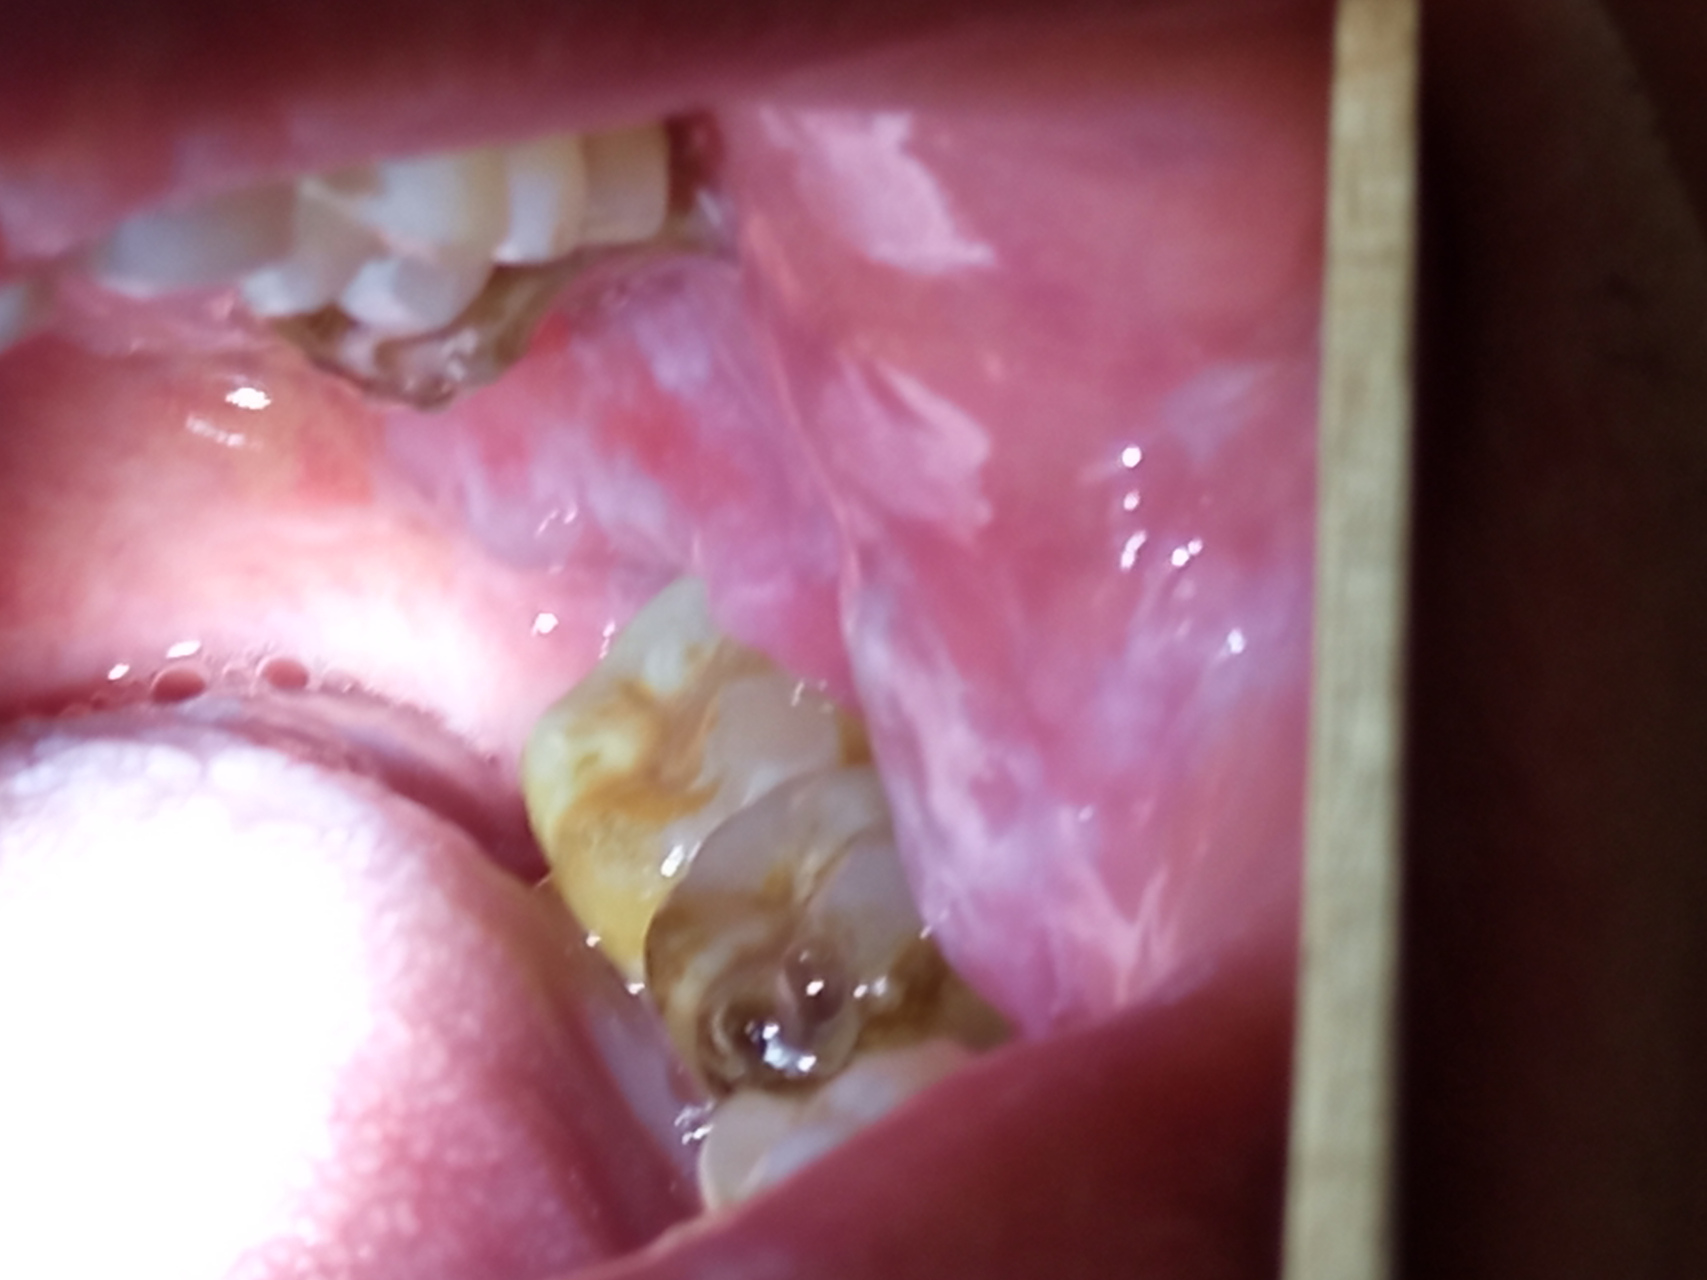

看一下患者颊粘膜 - 口腔医学专业讨论版 - 爱爱医医学论坛

【求助】口腔黏膜病变 [病例帖]

【病例讨论】口腔粘膜病变,求指导 [病例帖]